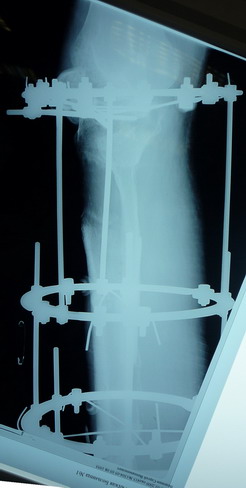

Пациент В. 53 лет, травма в феврале 2009. ДЗ. Открытый оскольчатый перелом нижней трети голени. При боли поступлении выполено ПХО, аппарат Илизарова. В последующем проводили ВХО, резекция костных отломков, укорочение 6 см, рана зажила. Была выполнена остеотомия большеберцовой кости в проксимальном отделе, резекция. Производилось тракция.

На последних рентгенограммах выявлено, что одновременно с "выращиванием" регенерата произошло низведение надколенника  на длину выращенного регенерата.

Клинически: активное разгибание сохранено, объем движений в колене 180-110 градусов.  Черными стрелками обозначен верхний край надколенника с одной и с другой стороны. Красная стрелка обозначает пальпируемую связку надколенника.

Причина - остеотомия выше места прикрепления связки надколенника.